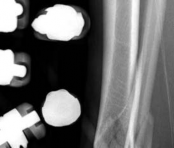

Temporary ankle-spanning external fixation was used to stabilize the fracture and soft tissues. X-rays taken after external fixation showed improved alignment and allowed for better understanding of the fracture pattern (Fig 2.2-2). Computed tomographic (CT) scanning with 3D reconstruction was performed for precise assessment of the fracture pattern of the tibial plafond. The CT revealed displaced fragments with a resultant intraarticular step-off and gap. The distal tibial metaphyseal fracture was multifragmentary. In addition, an associated long oblique fibular fracture was present (Fig 2.2-3).

Fig 2.2-2a–b Realignment of fracture through application of spanning external fixator.

1. AP view.

2. Lateral view.